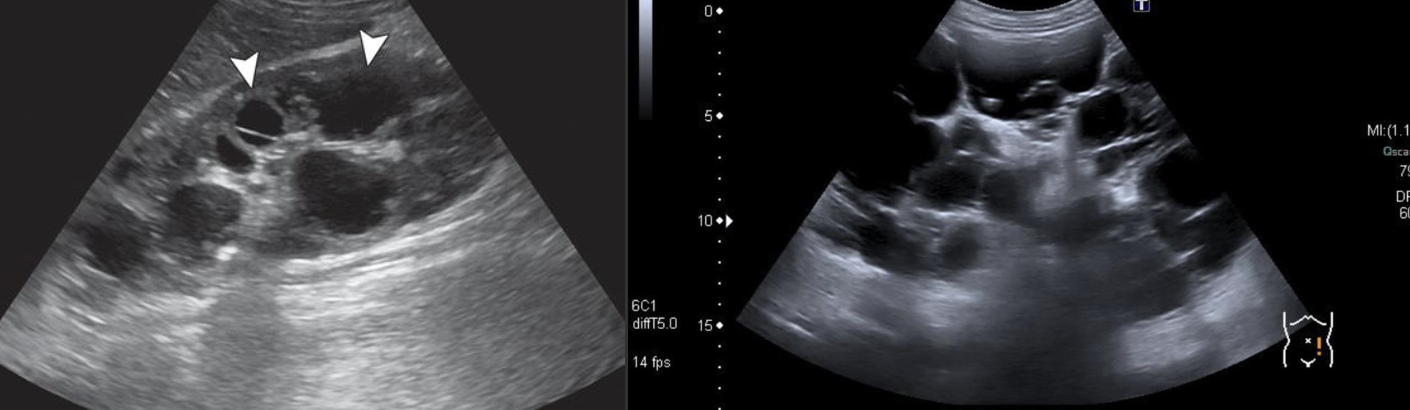

Polycystic Liver Disease → associated with ADPKD

clinical hx: ADPKD, female

s/sx: usually asymptomatic

2D US: varied multiple simple cysts, hepatomegaly from excessive cyst, cysts can become complicated (infected or hemorrhagic)

color doppler: avascular if uncomplicated

DDX: ADPKD, peribiliary cysts, simple cysts

ADPKD (Autosomal Dominant Polycystic Kidney Disease ) → most common hereditary kidney disorder

clinical hx: 30 y/o develops, associated with polycystic liver disease

s/sx: HTN, palpable masses, swollen abdomen, pain w/ rupture, bouts with kidney stones

2D US: bilateral cortical/medullary cysts, varying sizes, simple/hemorrhagic, enlarged bilateral kidneys, normal tissue replaced with cysts,

color doppler: focal echogenic vascular lesion in background of PKD

DDX: parapelvic cysts, hydronephrosis